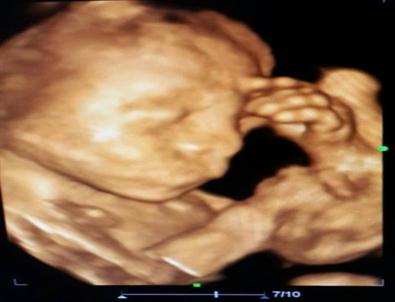

Anne Karnında Düşünen Bebek

Konya’da 23 haftalık bebeğinin anne karnında elini başına koyarak düşünen hali ultrason ile kaydedildi.

Konya’nın Ereğli ilçesinde bir anne adayının kontrol edilen 23 haftalık kız bebeği 4 boyutlu ultrason cihazında elini başına koyarak düşünürken görüldü.

Gördüğü manzara karşısında şaşıran Kadın Doğum Uzmanı Op. Dr. Kadriye Turgut bu anı ölümsüzleştirerek fotoğraf olarak kaydetti.

Anne karnında bebeğin annenin yaşadığı mutluluğu, sevinci, üzüntüyü hissediyor olarak bilinmesi, kaydedilen bu fotoğraf ile 'acaba bebek annesinden mi etkileniyor' düşüncesini akıllara getirdi.